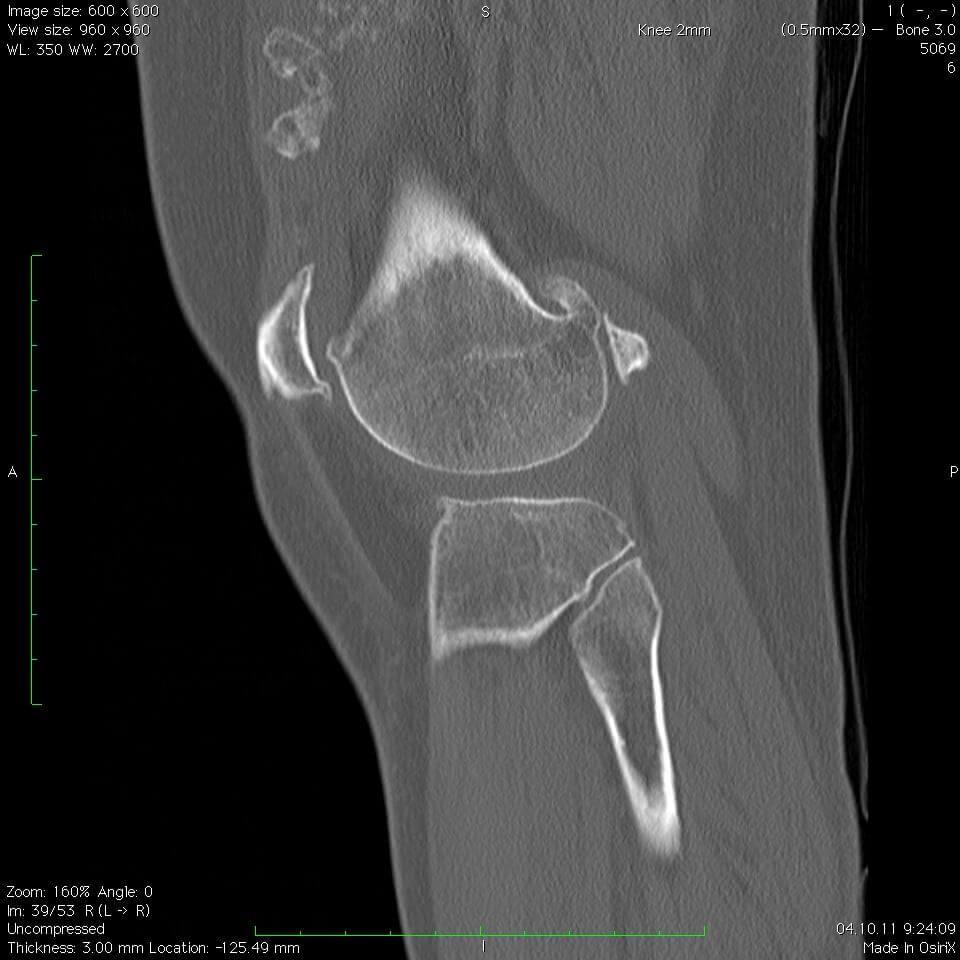

Постановка точного диагноза основывается на особых клинических проявлениях, а также на результатах проведенного инструментального обследования. Специалист в процессе исследования патологии и ее диагностики назначает такие процедуры, как:

- Рентгенография, в процессе которой делается снимок сустава. При наличии данного заболевания на нем отмечаются образование в виде эллипса или шара;

- Рентгенограмма коленного сустава, которая дает возможность определить не только разные образования, находящиеся внутри сустава, а также можно выявить скопления соли и кальция;

- Ультразвуковая диагностика;

- Компьютерная и магниторезонансная томография.

При необходимости проводятся разные дополнительные способы, позволяющие получить более точные детали о патологии – размеры образования, их расположение и количество. В особо сложных ситуациях врач может назначить диагностическую операцию. Сюда можно отнести такие процессы, как артроскопия или биопсия. Подобные процедуры дают возможность точно определить присутствие хондромных тел, проводится анализ общего состояния суставных поверхностей, а также основной синовиальной оболочки.